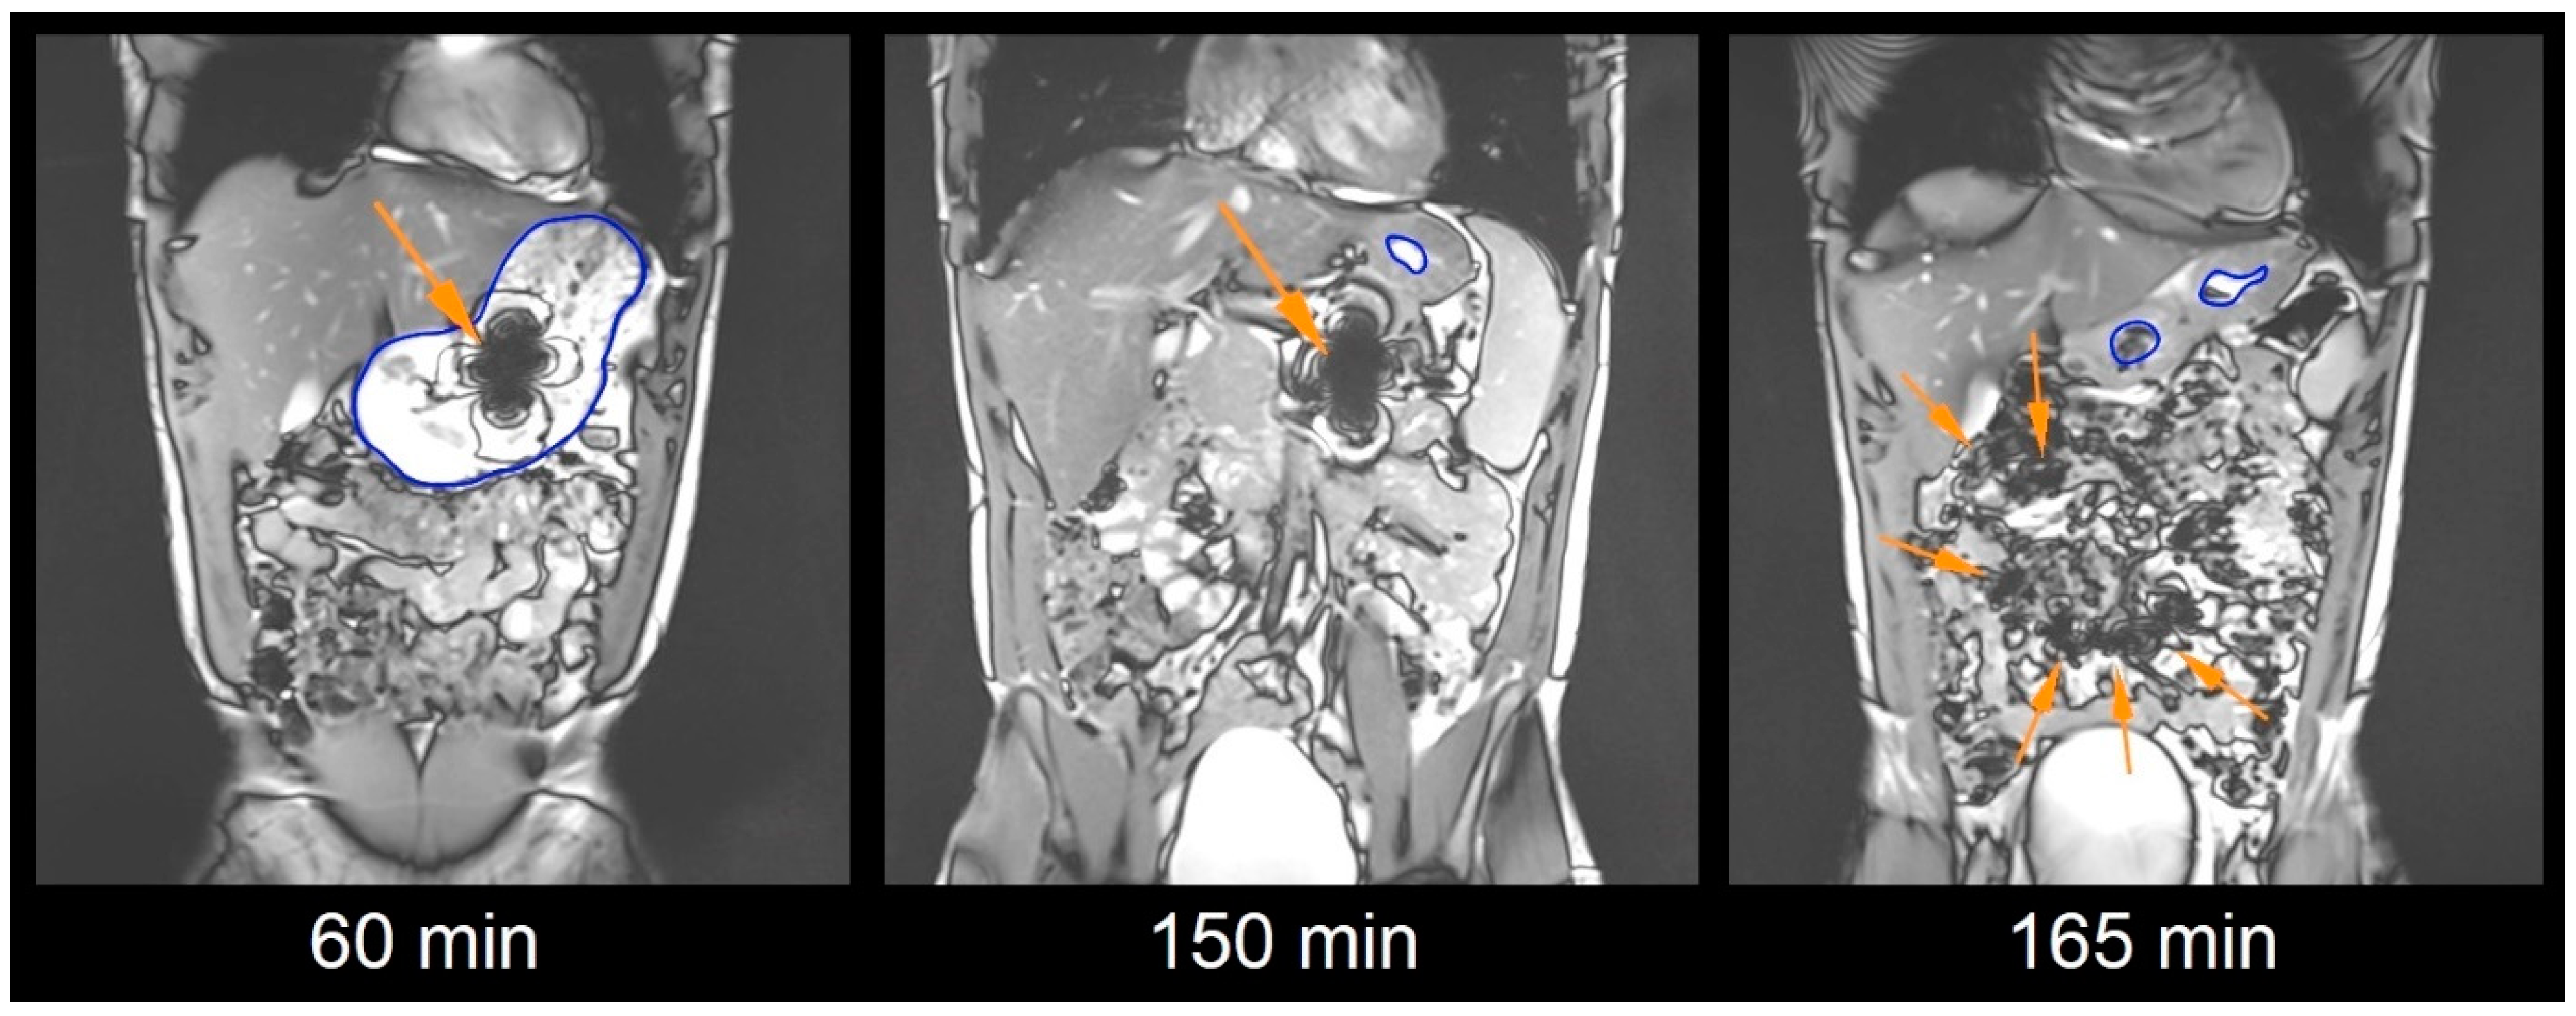

2.5. Magnetic Resonance Imaging Sequences

2.6. Image Analysis

2.7. Capsule Evaluation Criteria